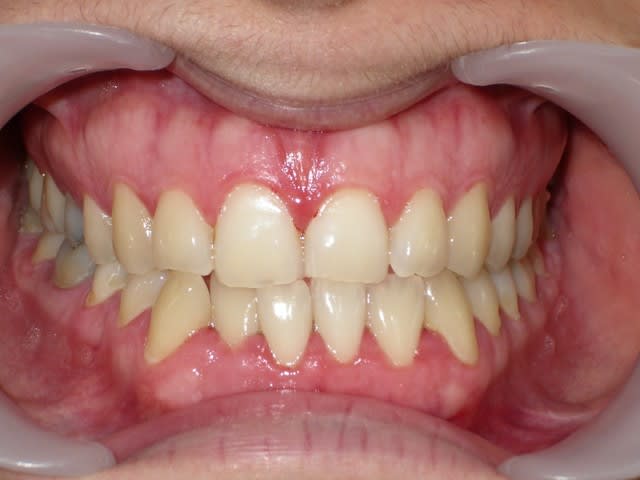

voici de la cas d'un jeune dame de 23 ans qui présente une full classe III subdivision Droite (associée à des compensations incisives de classe III), sur un terrain hyperdivergent. on note un encombrement inferieur d'environ 2 mm et une abrasion des bords triturants des incisives inf (Motif de la consultation)

"une abrasion des bords triturants des incisives inf (Motif de la consultation)"

c'est pas les incisives sup plutôt ?